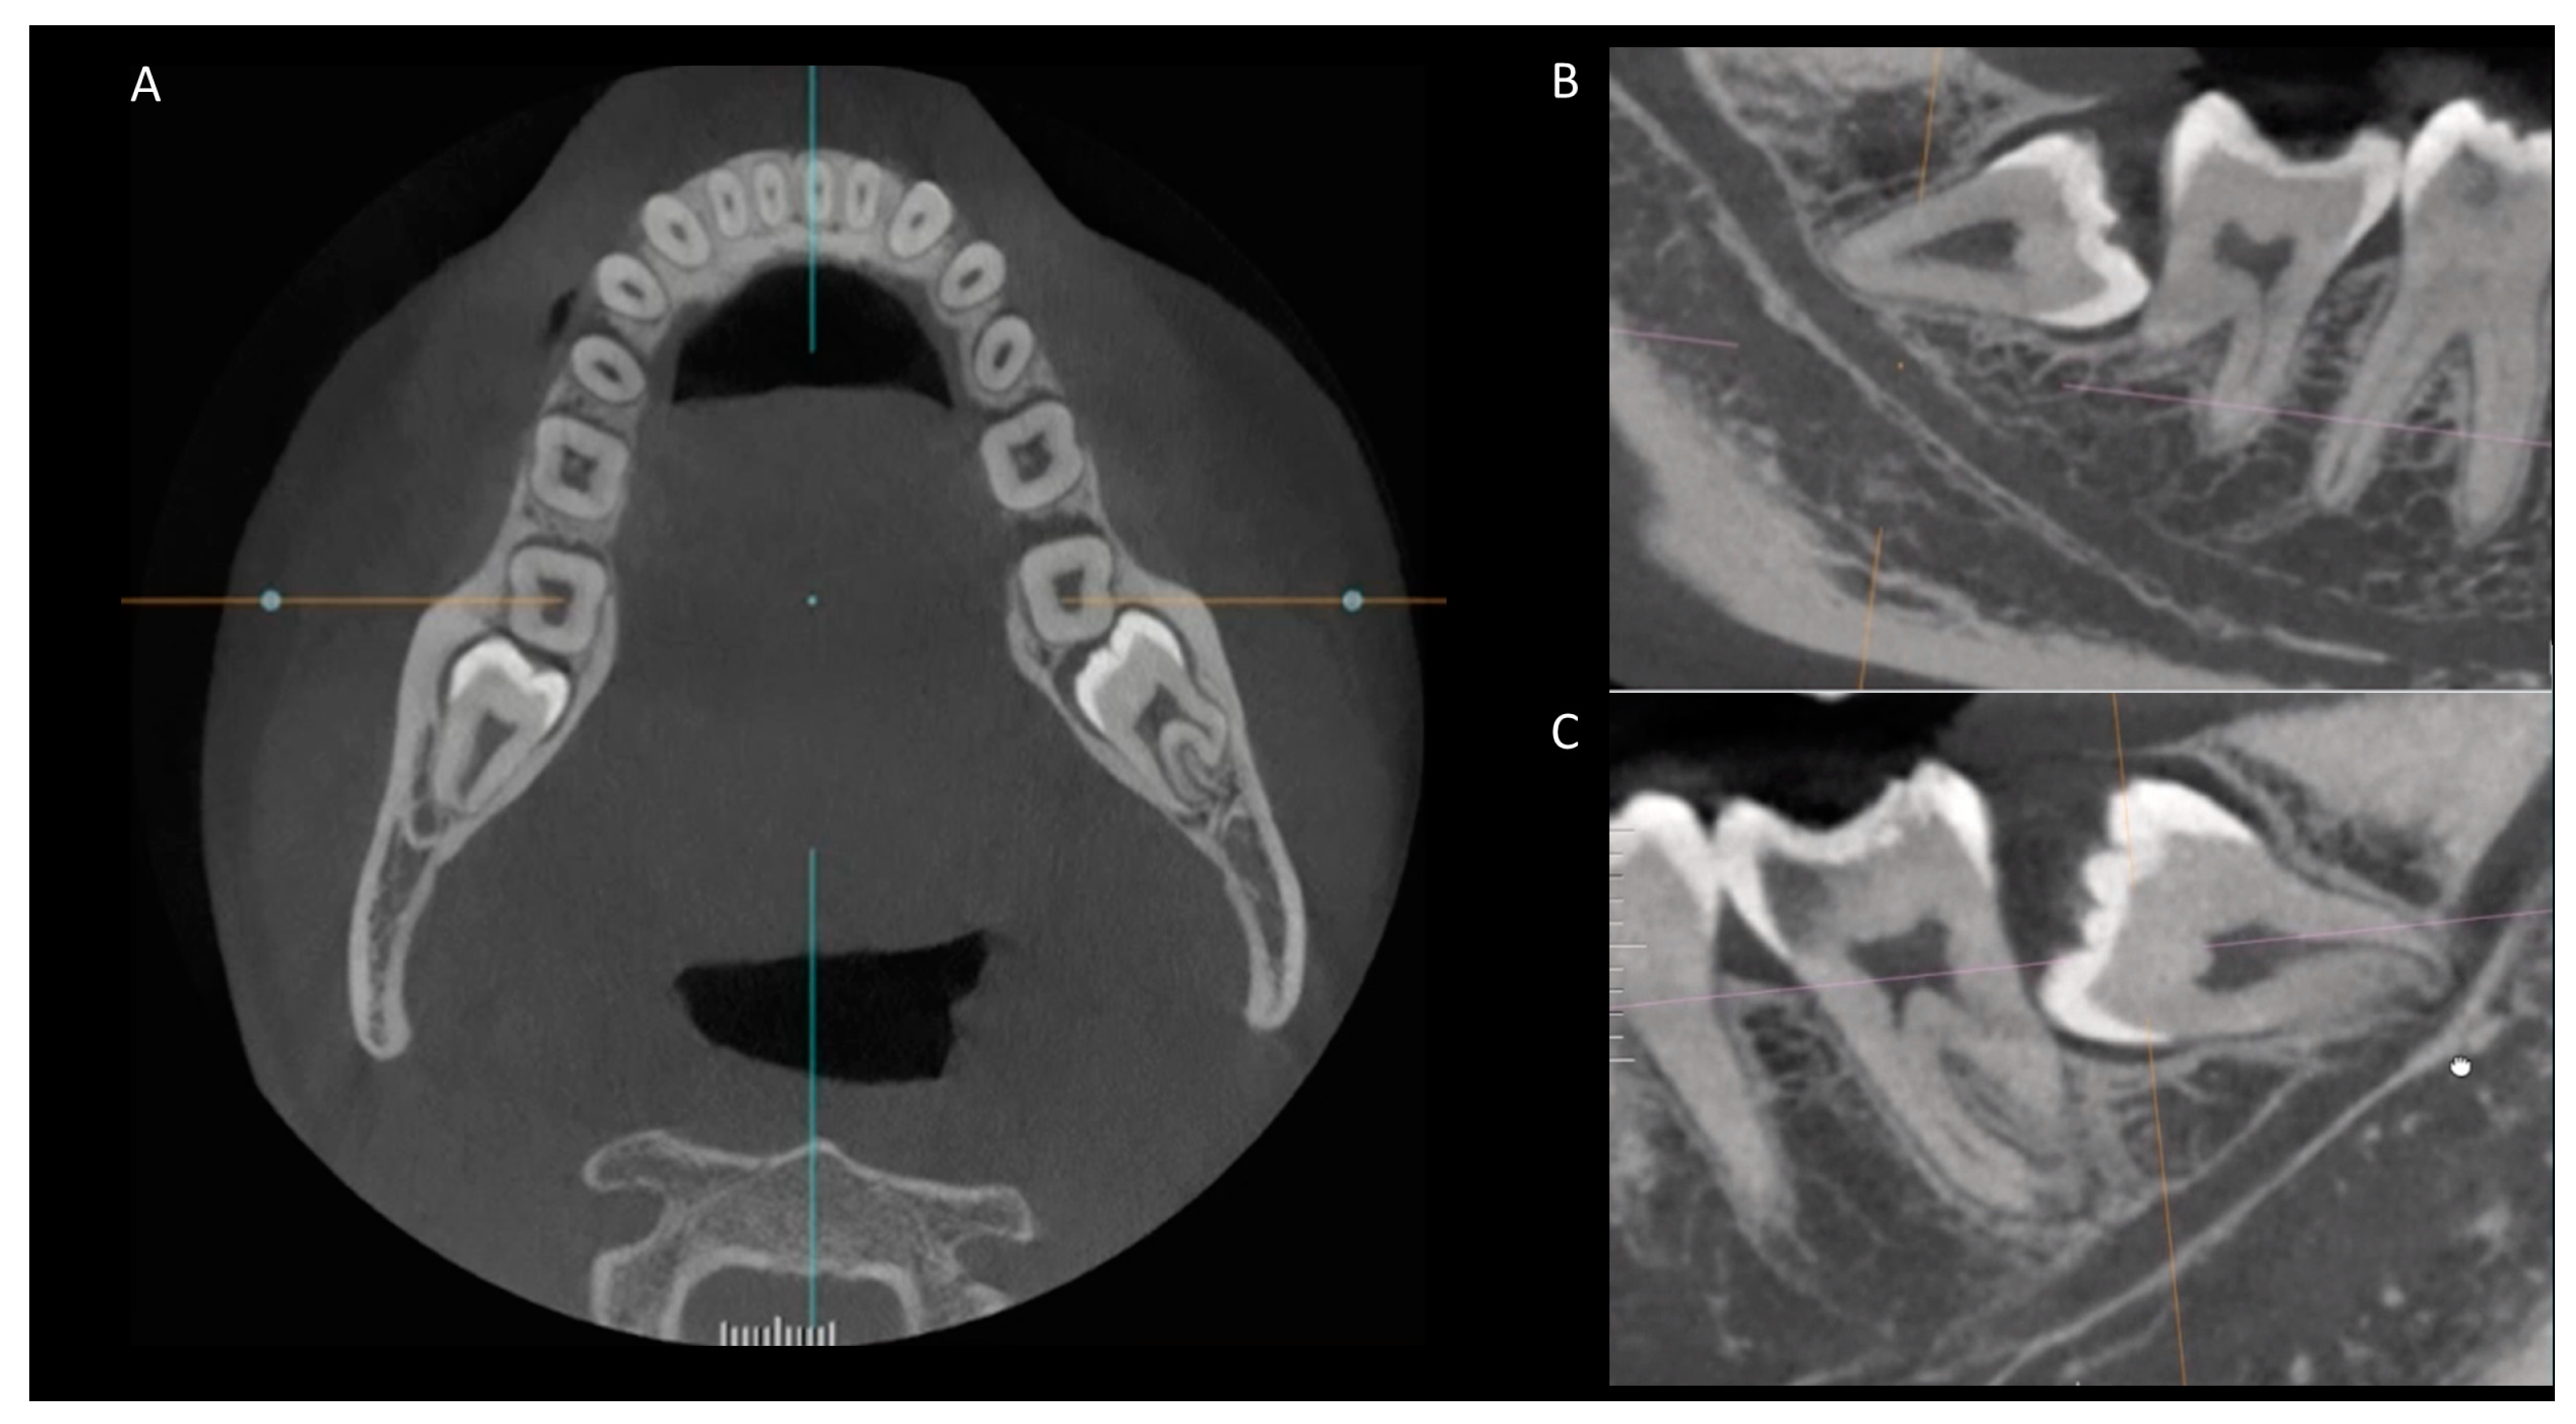

2. Materials and Methods

3.3. Anatomical Relationship between the Root Apex of the Impacted Third Molar and the Mandibular Canal

3.4. Occurrence of External Root Resorption on the Distal Side of the Mandibular Second Molar